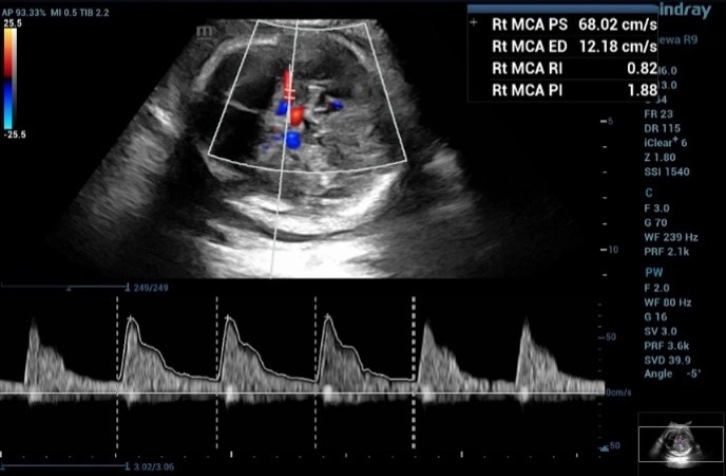

2. Middle Cerebral Artery Doppler for fetal anemia (Hb Bart's disease)

Fetal middle cerebral arterial (MCA) Doppler assessment is an important part of assessing fetal cardiovascular distress, fetal anemia or fetal hypoxia. In the appropriate situation it is a very useful adjunct to umbilical artery doppler assessment.

From the three MCA-PSV measurements in this fetus,

2nd MCA-PSV= 68.02 = 1.804 MoM (Figure 5)

the second measurement of the doppler waveform of MCA in fetus with and the MCA-PSV value was 68.02 cm/s, which is greater than 1.55 MoM

Figure 5 Shows the second measurement of the doppler waveform of MCA in fetus with and the MCA-PSV value was 68.02 cm/s, which is greater than 1.55 MoM